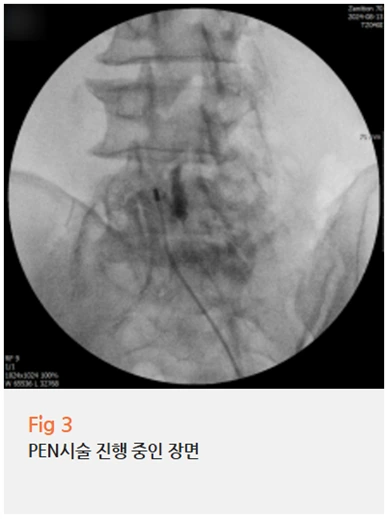

이분의 경우, 저는 PEN 시술을 권유드렸습니다.

PEN 시술, 어떤 치료인가요

PEN은 Percutaneous Epidural Neuroplasty의 약자로,

경피적 경막외 신경성형술이라고도 불려요.

가느다란 카테터를 경막외강 안으로 삽입해서,

신경 주변에 형성된 유착을 직접 풀어주고,

눌려 있는 신경 바로 주변에 약물을 정확히 투여하는 방식입니다.

기존의 주사 치료가 신경에서 떨어진 위치에 약물을 투여하는 것과 달리,

PEN은 문제가 있는 신경 바로 옆까지 접근한다는 점에서 구조적으로 달라요.

✔️ 유착된 신경 주변 조직을 박리해 신경 감압

✔️ 신경 바로 주변에 소량의 약물을 정확히 투여

✔️ 국소마취로 진행, 시술 시간도 비교적 짧은 편

✔️ 수술 없이 진행하는 최소침습적 치료